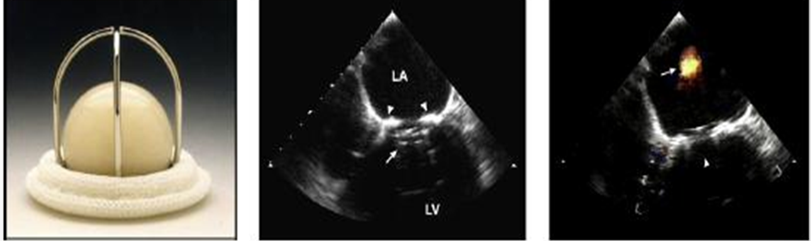

what is this?

ball in cage (starr edwards)

what kind of pressure gradients do ball cage prosthetic valves have?

HIGH pressure gradients

what is normal regurgitant volume for ball cage prosthetic valves?

2-6ml/beat